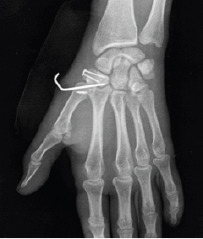

Radiographic study was performed (Fig. 1.1, 1.2), which revealed a fracture, with a deviation>2 mm, from the vertical dorsal trapezium edge fracture with more than 2mm deviation and a volar tubercle fracture without deviation, corresponding type IIb, and type III Walker fracture, respectively. A comminuted Bennett fracture with associated trapezium-metacarpal dislocation was also diagnosed. This lesion was then subjected to computed tomography (CT) evaluation (Fig. 2.1, 2.2) for a better characterization of the fracture pattern with regard to joint deviation, number and size of fragments, and their respective spatial orientation.

Figure 1.1.

X-ray: Anteroposterior view.

Figure 1.2.

X-ray: Oblique view.